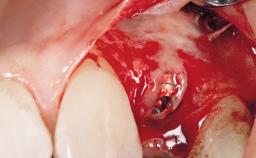

A 30-year-old female patient was referred to the office for the treatment of tooth 11. Her chief concern at the initial visit was to inquire, “Why is my tooth pink?” Upon clinical examination, it was determined that tooth 11 had a previous history of trauma and that the clinical crown had become noticeably pink in color as a result of internal resorption. This diagnosis was confirmed radiographically, indicating a large radiolucency involving the central and distal portions of the clinical crown. It was determined that restoration of this tooth was not possible, and that extraction was indicated. The presence of a mid-line diastema, which the patient wanted to reproduce, directed the treatment plan for tooth replacement utilizing a dental implant.

Bone Augmentation Horizontal|Simultaneous

Augmentation Materials Autogenous chips|Membrane

Placement Protocol Immediate implant placement

Socket Integrity Sufficient, with intact bone walls

Bone Volume Sufficient, with intact walls